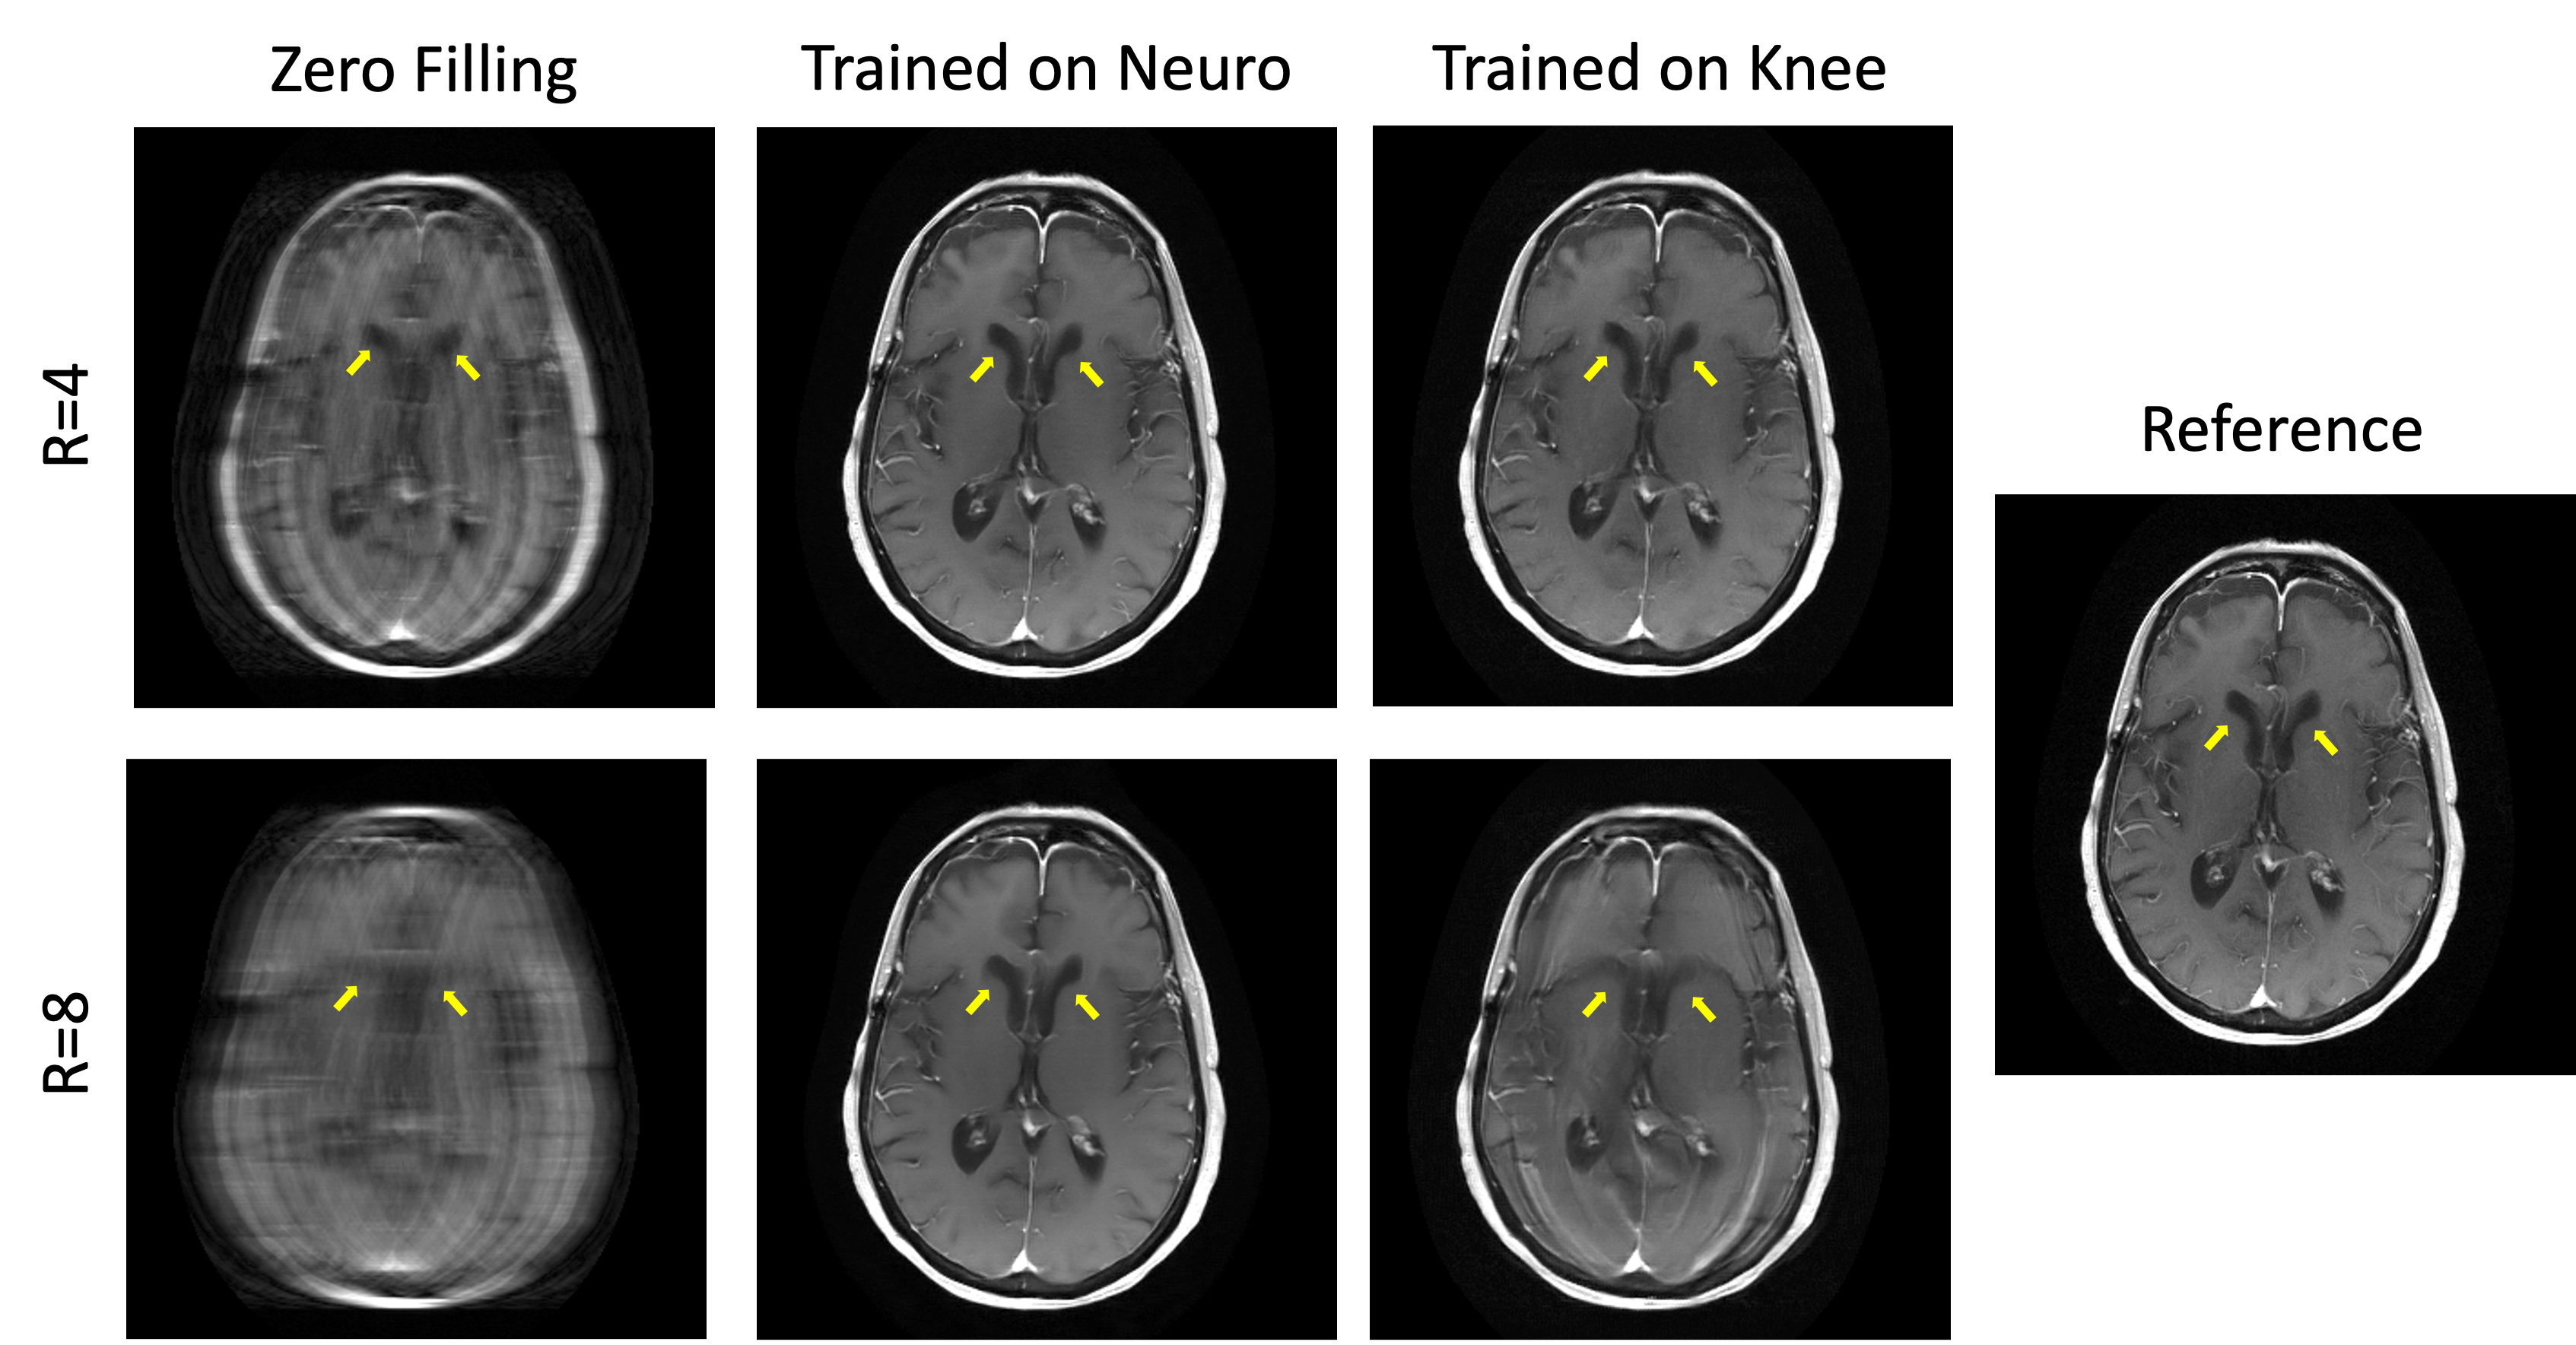

However, even physics-driven deep learning methods face some challenges for accelerated MRI. The impact of domain shift, i.e., training and testing on different data was studied in [58], for different acceleration factors. All training and evaluation is based on the fastMRI knee and neuro datasets [73]. While for acceleration 4, the proposed Down-Up networks with varying data consistency layers generalize well for both anatomies, the type and amount of training data becomes more critical for acceleration factor 8. Since fewer data is available for data consistency at this acceleration, the networks start to reconstruct anatomical structures that are not real. When trained on a subset of knee data and applied to neuro data, the ventricles start resembling knee structures, for acceleration 8 as depicted in Figure 4.